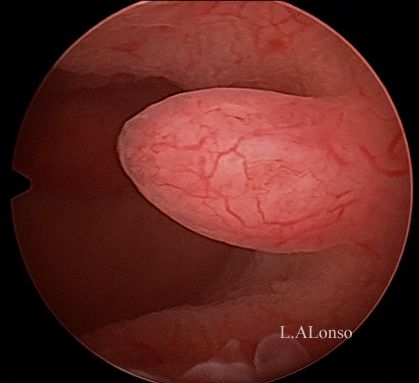

Q.14. What do you see?

Correct Answer : D

Q.15. What's the finding?

Correct Answer : B

Q.16. What's the diagnosis?

Correct Answer : A

Q.17. What's the finding?